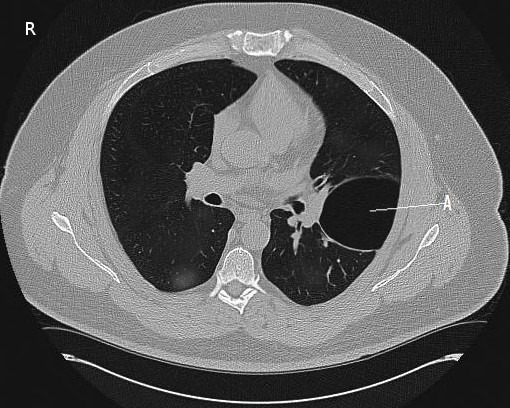

그림